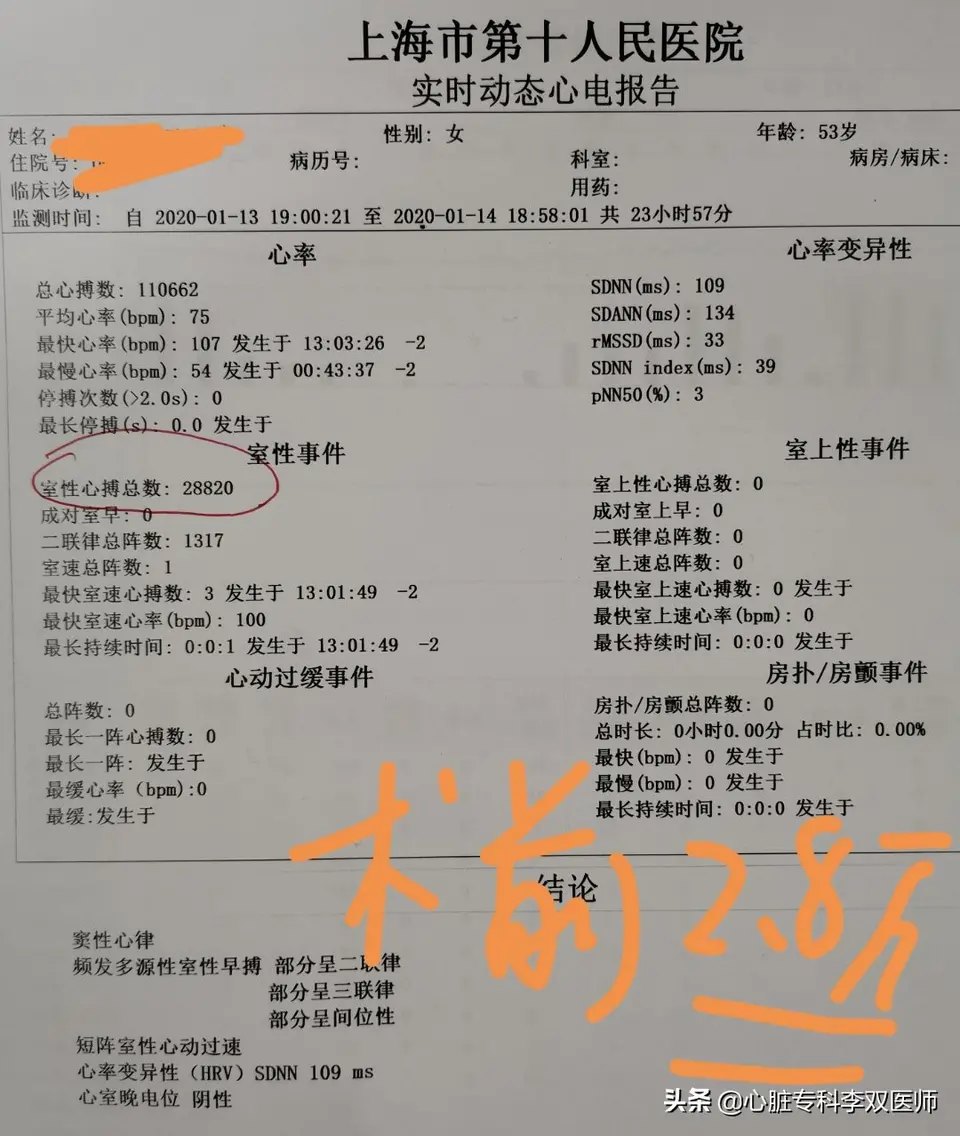

前天给一个外地来就诊的病人做了难度很高的“心外膜室早”消融的病例,病人一年前在杭州某三甲医院曾行消融失败,这一年来因为笼罩在“频发室早”的阴影下,患者有了明显的心理问题。这次我们标测的情况和上次外院消融情况完全一致,只是坚持又带有一点运气的在非传统的消融位置(解剖位置,而不是最早激动位置)尝试了消融,结果异常的顺利,术中忐忐忑忑观察了一小时无复发。今天患者顺利出院,术后24小时心电图提示的室早仅2次(一天的心跳是约10万次,1000次以内的早博没有意义),比机器的误差都小,而术前是1.4—2.8万次,是万!万!万!。坚持就是胜利,坚持带来好运!